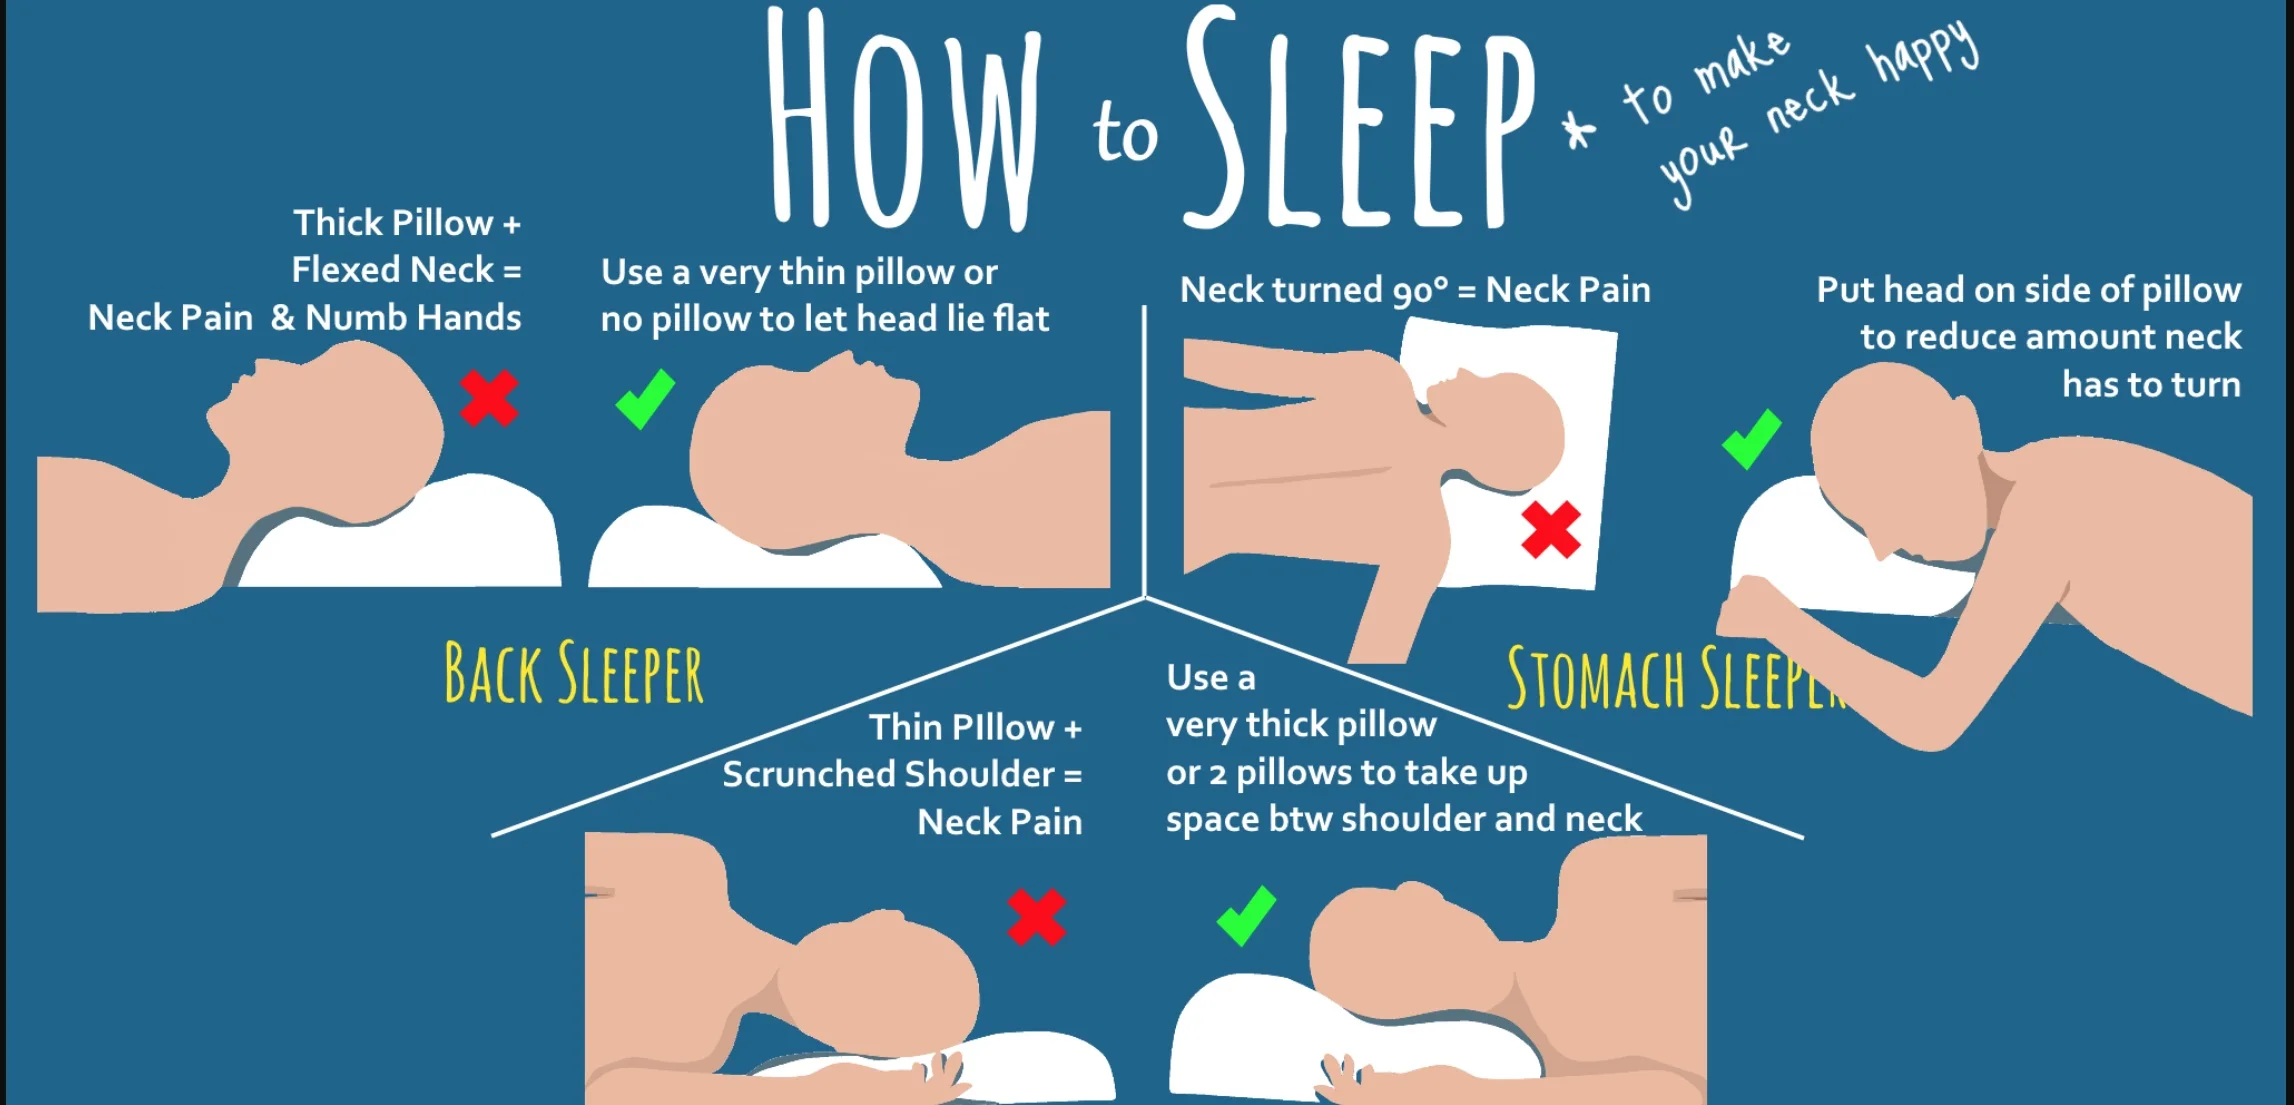

Neck Pain Perth Sports Chiropractor Bassendean WA